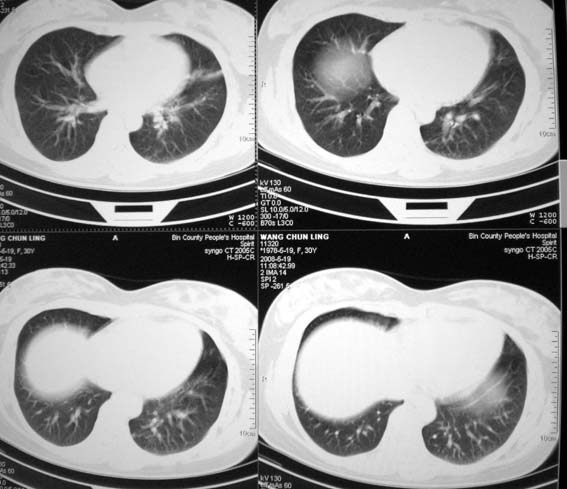

女,30岁,怀孕后3个月,拍片时肺结核,抗结核治疗4个月复查。

前段支气管通畅,但尖后段支气管闭塞,建议支纤镜除外肺癌,有原片吗,对比一下了。

结核.前段支气管通畅,但尖后段支气管闭塞,建议支纤镜除外肺癌

纵隔淋巴结肿大,见意出外占位